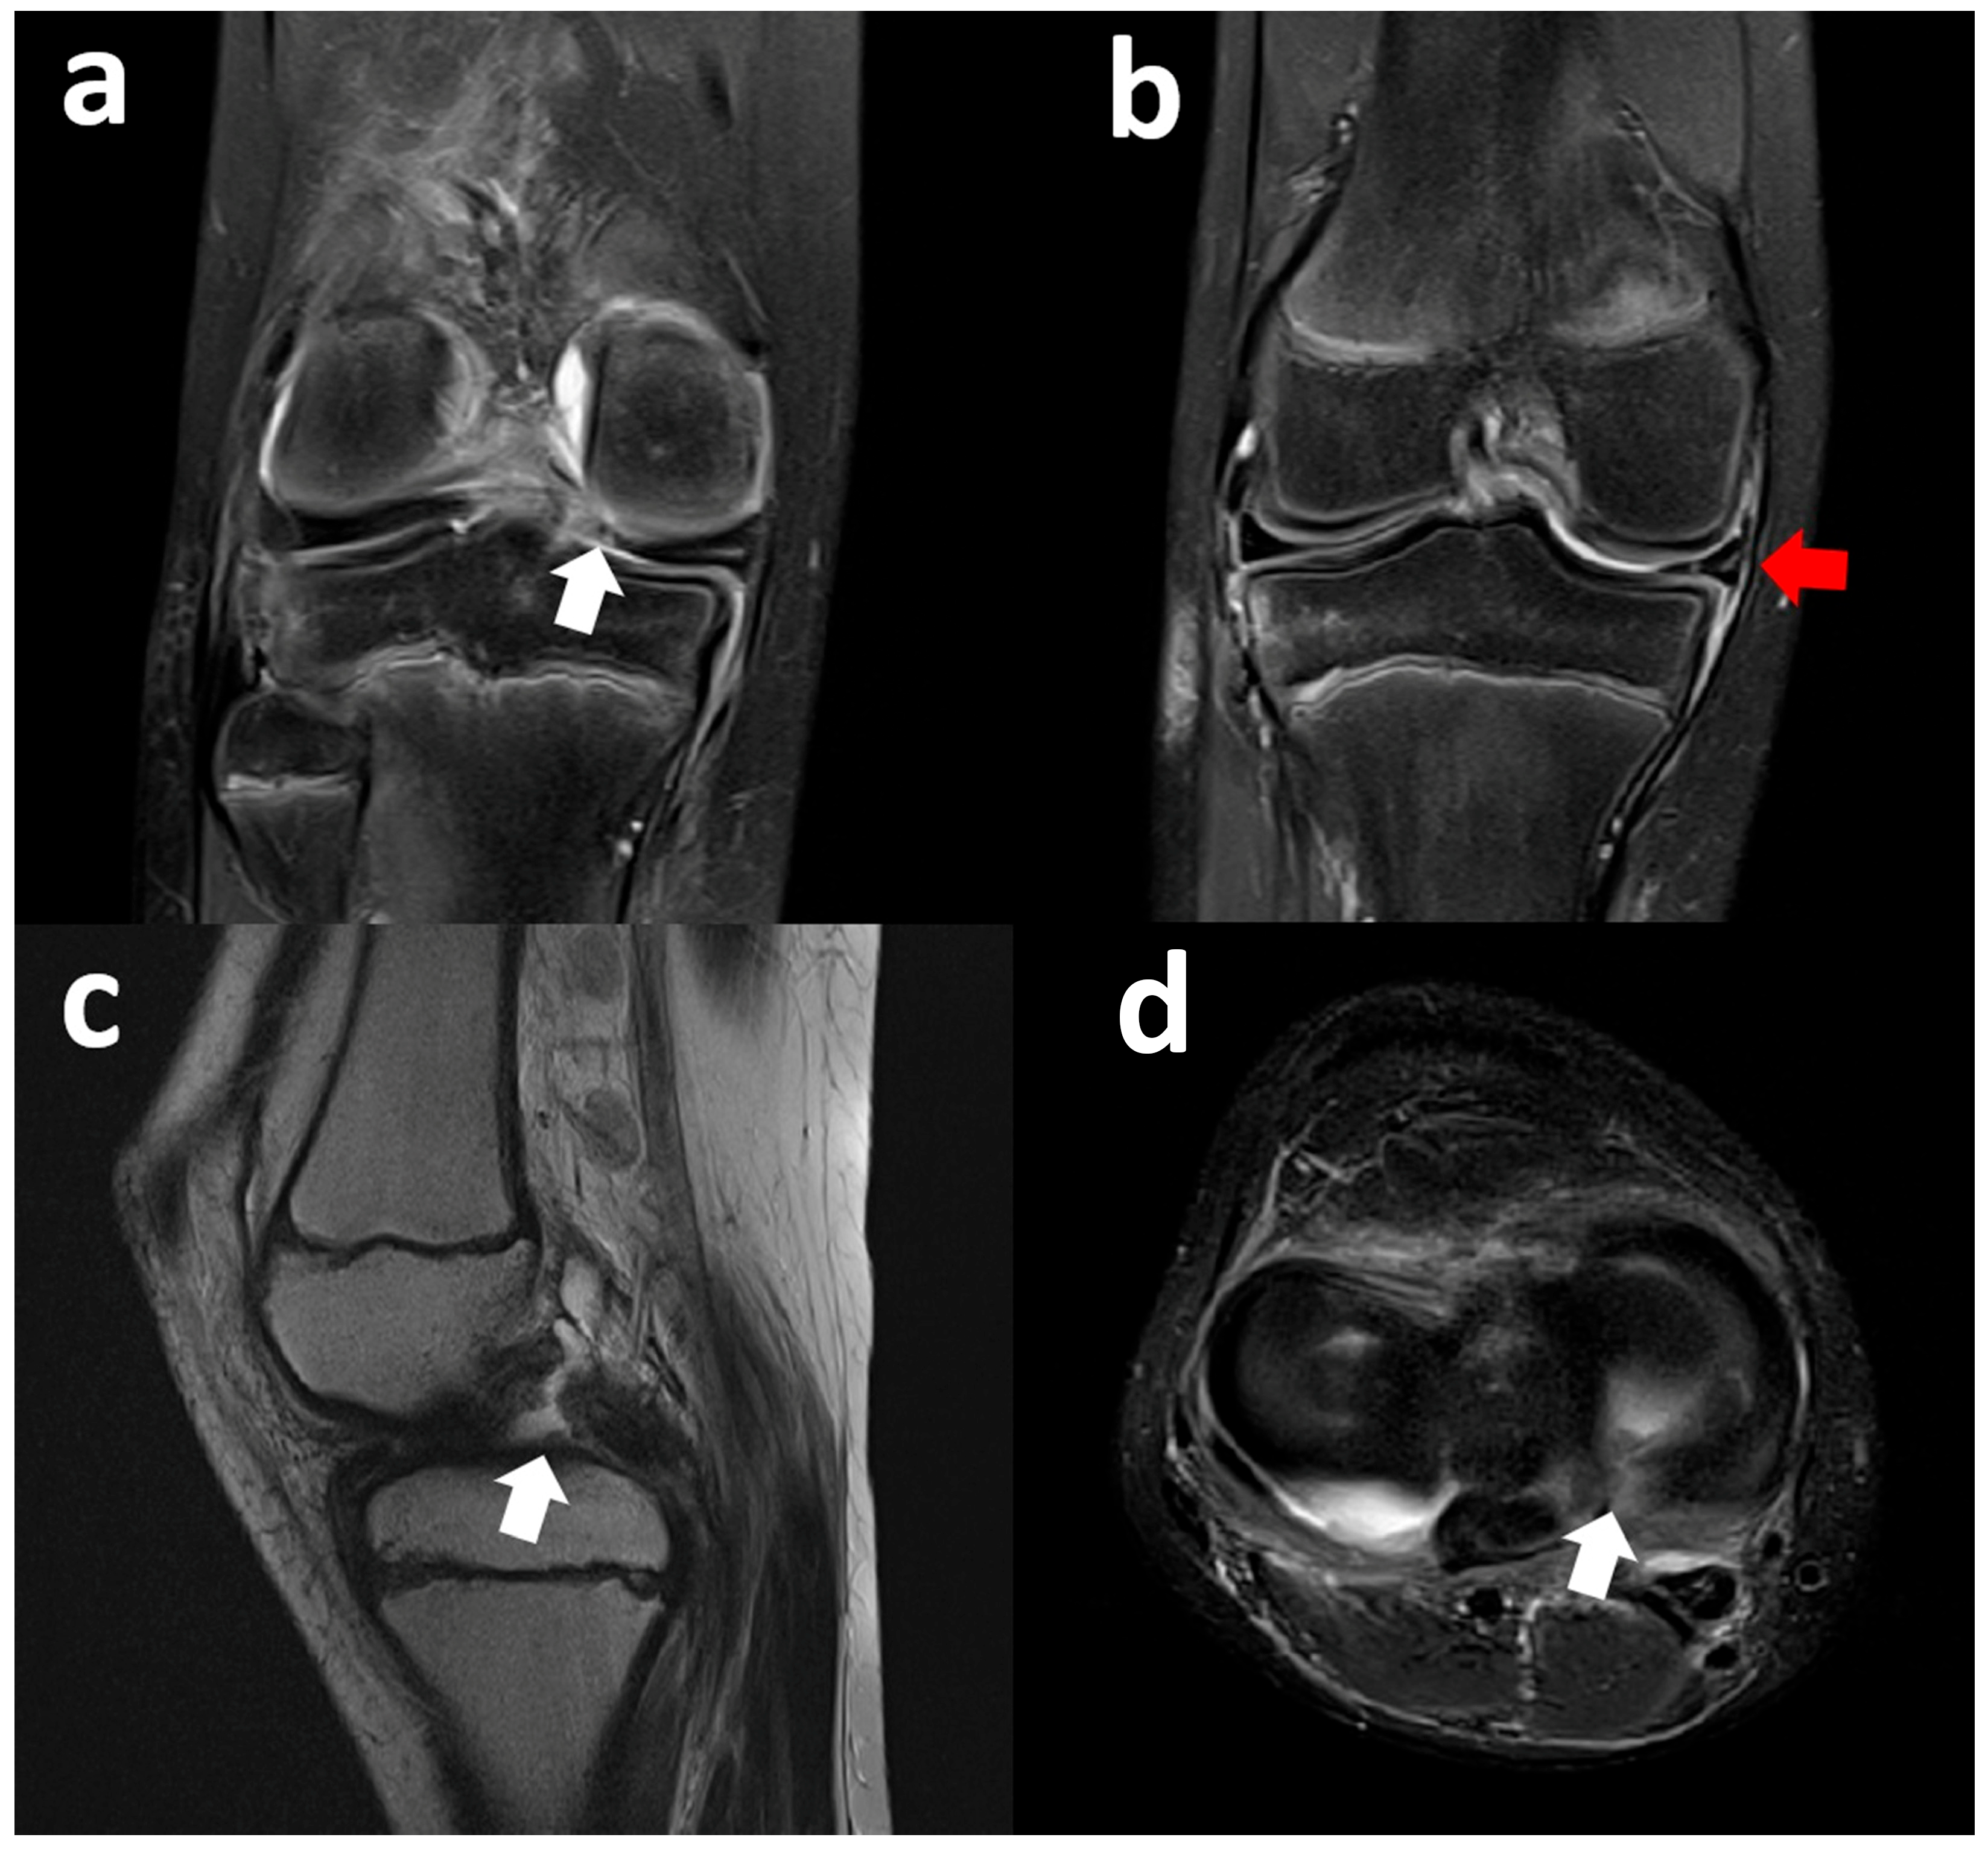

3.5. Lateral Meniscus Flipped in the Lateral Gutter

3.6. Lateral Meniscus Posterior Root Tear with Extrusion

3.7. Lateral Meniscus Body Within Tibial Plateau Fracture